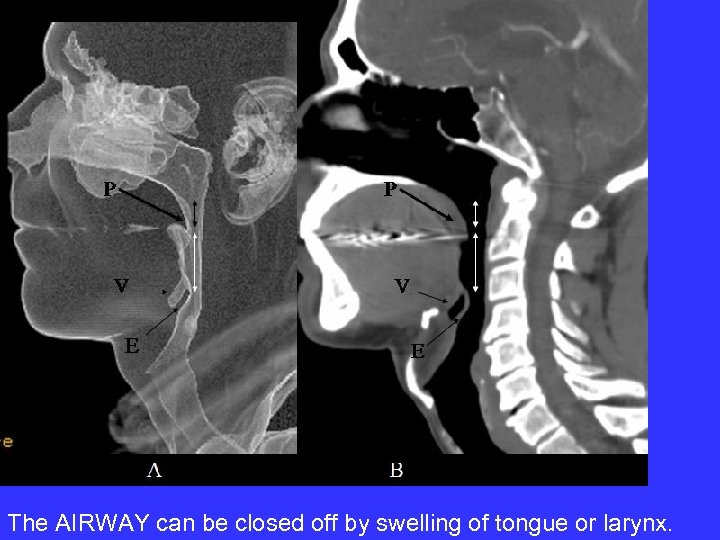

The AIRWAY can be closed off by swelling of tongue or larynx.